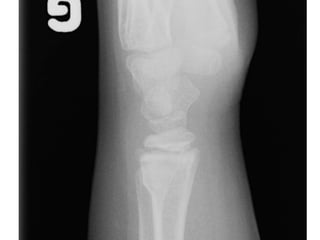

Diagnostic ?

A. Salter 1

B. Entorse cheville

C. Entorse haute

D. Salter 3

E. Avulsion

Fracture de Tillaux

• Salter 3

• Fracture de la portion latéral de

l’épiphyse du tibia distal

• La portion médiane de la physe du tibia

ayant déjà commencé à se fusionner

Conduite

• Atelle postérieure

• Référé 24 heures

• Aviser résident de garde ortho